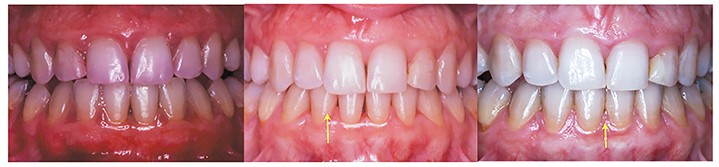

L’objectif de cette séance est d’apporter une vue actualisée, claire et précise, nécessaire au dépistage, à la motivation et aux techniques des traitements parodontaux, et de faciliter leur intégration dans l’exercice omnipratique (fig. 4, 5 et 6).